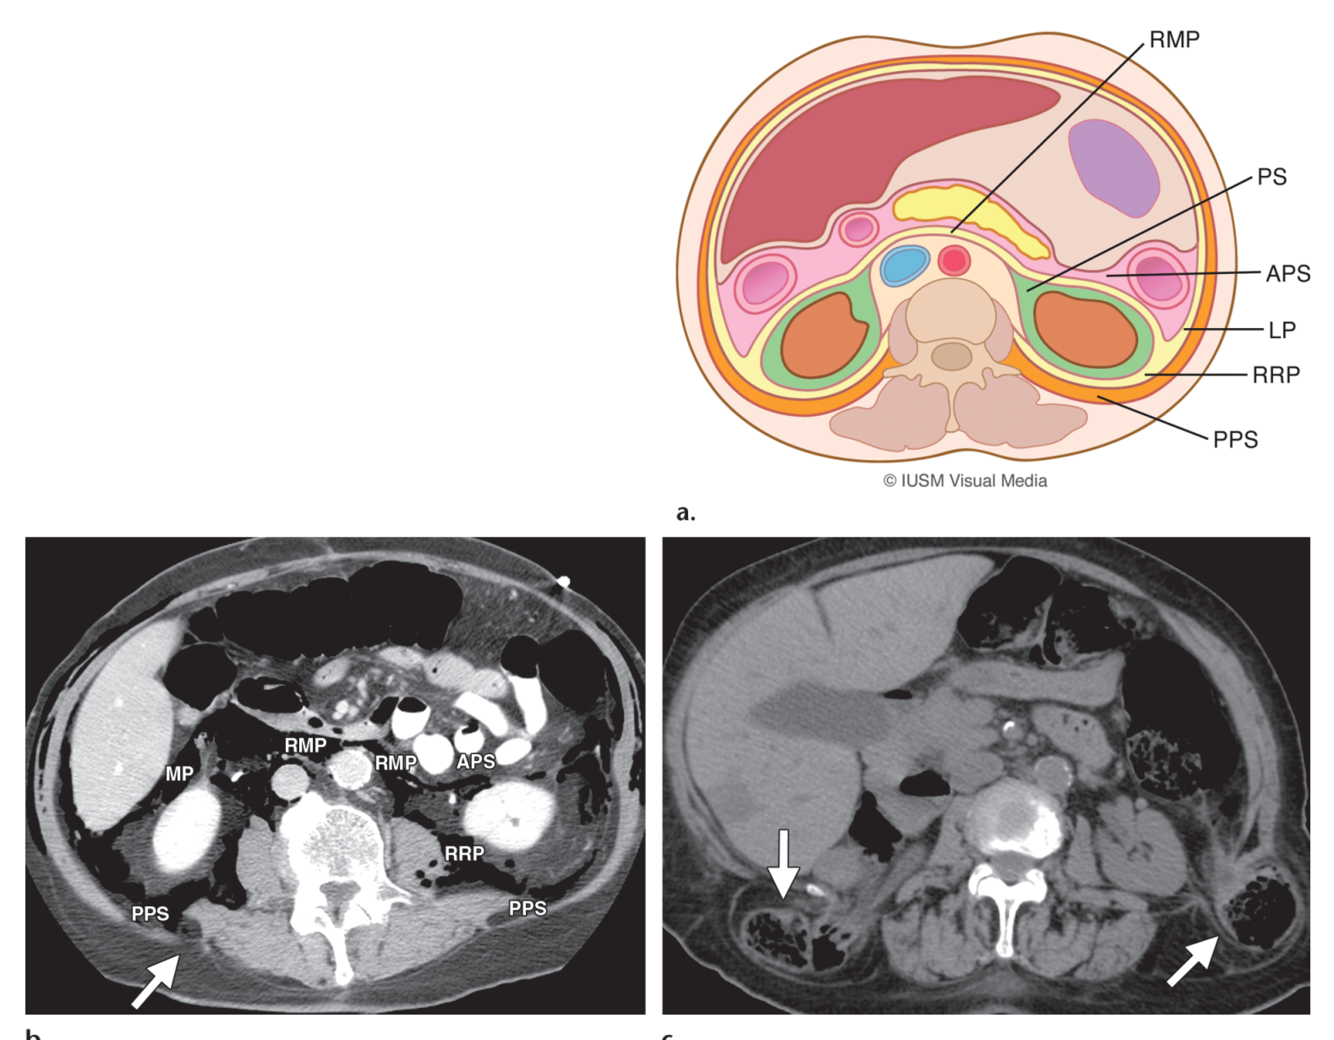

Anterior interfascial retromesenteric plane.

Potentially expansile plane between the anterior pararenal space and perinephric space ; continuous across the midline.

It is an important potential route of contralateral spread of retroperitoneal collections.

Posterior interfascial retrorenal plane.

Combined interfascial plane.

Fig. 2: Sagittal CT image shows inferior fusion of retromesenteric plane (RMP) with retrorenal plane (RRP) to form the combined interfascial plane (CIP). This point creates a route for spread of diseases between the abdominal and pelvic retroperitoneal spaces

Fascial trifurcation. Site at which the LCF emerges from Gerota fascia; anterior, posterior, and lateroconal interfascial planes communicate at the fascial trifurcation, usually located laterally to the kidney.

Anterior pararenal space

Between parietal peritoneum and anterior renal fascia ; contains pancreas and bowel

Perirenal space.

Between anterior renal fascia and posterior renal fascia

Contains kidney, adrenal gland, proximal collecting systems, renal vessels, and a variable amount of fat

The perinephric spaces are closed medially.

The retromesenteric space is continuous across midline.